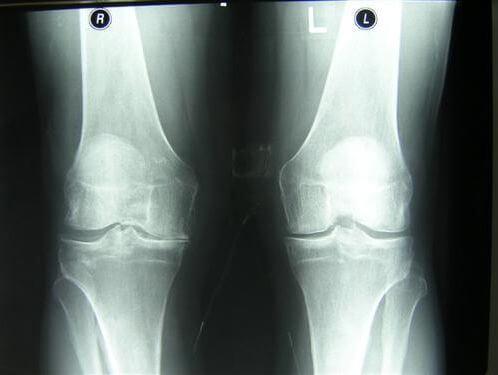

And here are pictures of joints before and after being treated with Maxiflex .

Woman. 54. The joint fully recovered.

Treatment period 1.5 months

The photos clearly show that Maxiflex doesn’t just alleviate the pain,but also starts the processes of regeneration of the synovial fluid - the function chondroprotectors are meant to perform. As a result, the cartilage layer becomes wider and more elastic - the joint improves, pain and stiffness disappear.